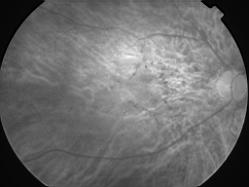

ASSOCIATION STRIES ANGIOIDES ET DYSROPHIE MACULAIRE RETICULEE

NEOVASCULARISATION